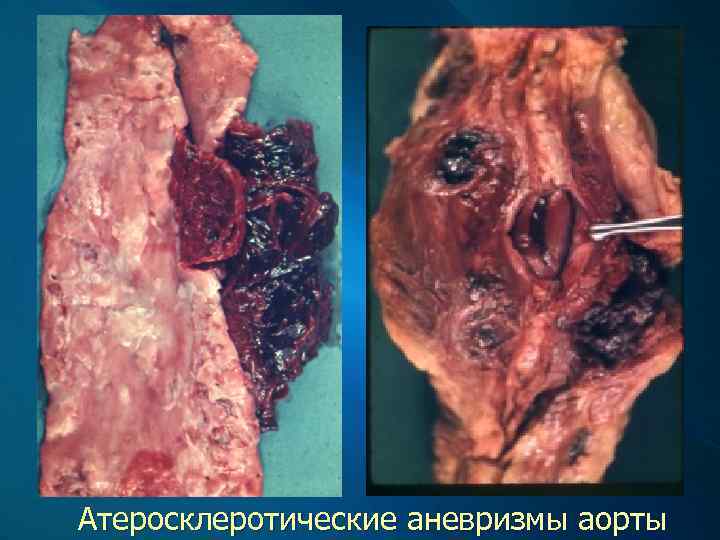

Клинические проявления и осложнения Атеросклероз аорты клинически значимых проявлений не имеет. Осложняется развитием аневризмы аорты, чаще в брюшном ее отделе, тромбозом в области ее бифуркации (синдром Лериша), эмболией (атероматозными и тромботическими массами) ее ветвей, что проявляется инфарктами почек и внезапной гипертензией и некрозами (инфарктами) кожи на пальцах стоп.

Осложнение атеросклероза: аневризма брюшного отдела аорты

Атеросклеротические аневризмы аорты